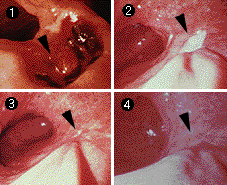

潰瘍の治る過程(内視鏡撮影) [1]出血のある活動性胃潰瘍[2]白苔(はくたい)をかぶっている胃潰瘍[3]治りかけの胃潰瘍。縮小してきている[4]潰瘍が治ったあと{瘢痕(はんこん)} |

胃潰瘍の進行 深い潰瘍になるほど治りにくく、治ったあとのひきつれ(瘢痕)もひどくなる。再発もしやすくなるので、早期治療が大切 |